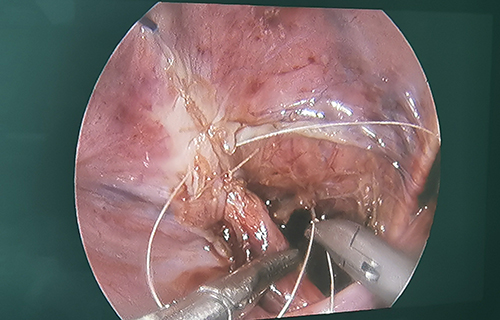

3个小时手术,完成再植

术前准备完毕。10月15日,栾志勇主任、谢方达副主任为佳佳行输尿管远端狭窄微创手术,在其肚脐周围打了3个直径5mm的小孔,在腹腔镜下顺利实施了输尿管膀胱再植。手术用时仅为3小时,出血量也比较少。

“如果开刀手术,需要在腹部做横切口,对孩子的损伤是比较大的。在保证手术效果的基础上,微创手术对孩子的损伤小,美观程度良好,术后恢复比较快。”栾志勇主任说。